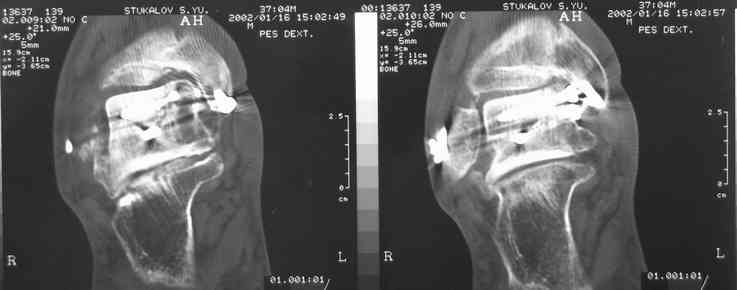

Случай с множественным оскольчатым переломом тарана оперированный из двойного доступа.

Через 2 мес.:

Через 8 мес.:

Через 14 мес.:

Два фрагмента суставной поверхности тарана можно восстановить боковой компрессией шурупами и дополнительно костная пластика.

(кстати, на нашем случае была применена костная пластика-allograft crouton для заполнения дефектов)